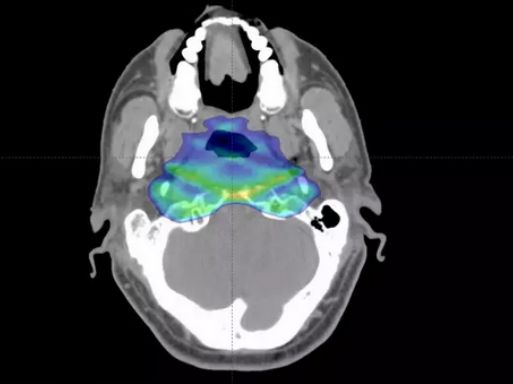

患者:男,55岁,因鼻塞2年余,涕中带血半年,头痛20余天,于2006年1月7日入院,诊断为鼻咽癌(低分化鳞癌)复发,给予质子治疗。每天一次,每次44C戈瑞,共20次,总剂量20*44=88戈瑞。

质子治疗剂量分布

治疗1个月后复查,肿瘤明显缩小,无不良反应

治疗7个月后MR图像,肿瘤缩小70%